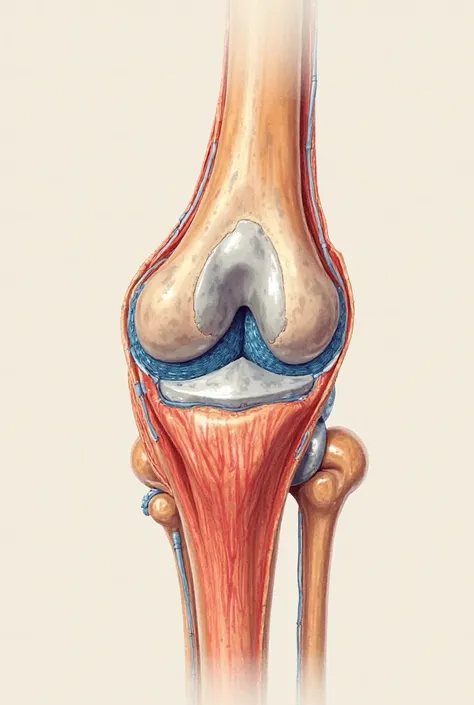

A close up of a white object with a human leg

Close-up of human knee,There is a bone in the middle, knee, Knees, surreal bone structure, Protruding bones, Realphotos, orthographic view, Look across the shoulder, medical depiction, Osteoarticular joints, computer generated, hyper realisitc, sharp bone structure, joint, digital painted

medical depiction

Osteoarticular joints